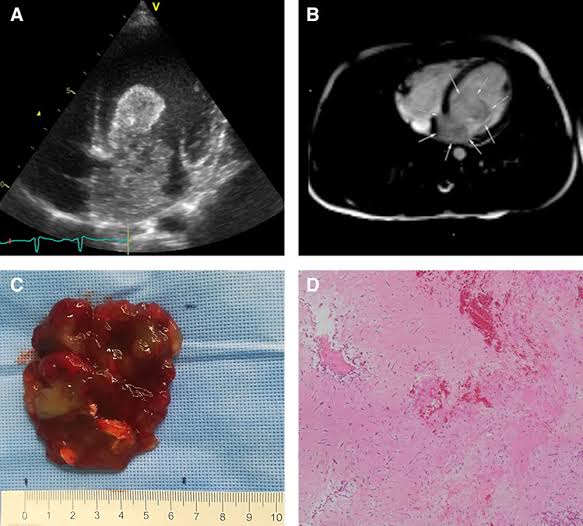

التصوير بالموجات فوق الصوتية عبر الصدر هو الخطوة الأولى في العديد من الحالات، حيث يُظهر صورًا تفصيلية للقلب ويمكن أن يكشف عن وجود ورم في الأذين الأيسر. إذا كانت النتائج غير واضحة، يتم اللجوء إلى التصوير بالموجات فوق الصوتية عبر المريء، والذي يوفر رؤية أكثر دقة للقلب والهياكل المحيطة به.

في بعض الحالات، يمكن استخدام التصوير بالرنين المغناطيسي أو التصوير المقطعي المحوسب لتوفير صور ثلاثية الأبعاد أكثر تفصيلاً. هذه الفحوصات تساعد في تحديد حجم وموقع الورم بدقة، وكذلك مدى تأثيره على الأنسجة المحيطة والصمامات.

تتعدد الفحوصات الطبية المستخدمة لتشخيص ميكزوما الأذين الأيسر، وتتنوع بين الفحوصات التصويرية والاختبارات الوظيفية. من أهم الفحوصات الطبية هي التصوير بالموجات فوق الصوتية للقلب، سواء عبر الصدر أو عبر المريء، حيث توفر هذه التقنية صورًا تفصيلية للأذين الأيسر وتساعد في كشف وجود الأورام.

التصوير بالرنين المغناطيسي للقلب يعتبر أيضًا أداة فعالة في التشخيص، إذ يقدم صورًا ثلاثية الأبعاد وعالية الدقة تُمكن الأطباء من تحديد حجم وموقع الورم بدقة. هذه التقنية تتيح رؤية واضحة للأوعية الدموية والهياكل القلبية، مما يساعد في تقييم تأثير الورم على تدفق الدم.